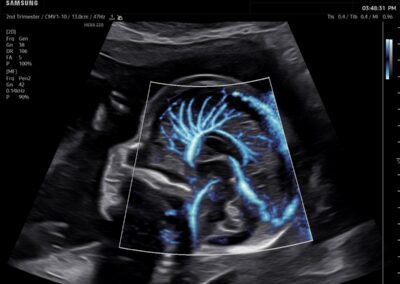

Procedural Services

Comprehensive, advanced and expert MFM care for high-risk pregnancies

- Fetal anomalies